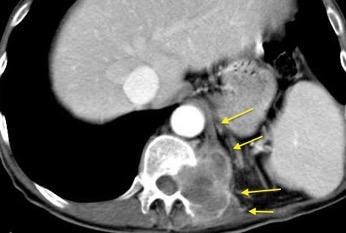

T. mixto de células germinales del testículo izquierdo

Nódulos pulmonares múltiples. (flechas verdes). Masas paratraqueales. (flechas amarillas). Dudoso ensanchamiento retrocrural (flechas negras). sigue….

Ttawfik A et al. Trans-diaphragmatic Pathologies: Anatomical Background and Spread of Disease on cross-sectional Imaging. Current Problems in Diagnostic Radiology. 2021.

T. mixto de células germinales del testículo

izquierdo Metástasis pulmonares. (flechas verdes). Ganglios paratraqueales. (flechas amarillas). Ganglios retroperitoneales (flechas negras)

Tawfik A et al. Trans-diaphragmatic Pathologies: Anatomical Background and Spread of Disease on cross-sectional Imaging. Current Problems in Diagnostic Radiology. 2021.